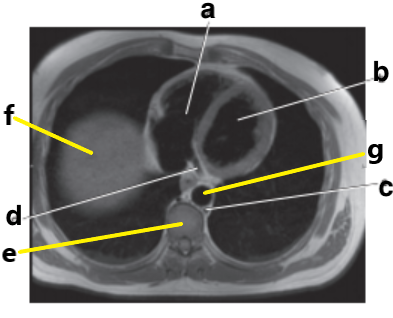

What is letter a ?

Right ventricle

What is letter d ?

What is letter f ?

Diaphragm

Ascending aorta

What is letter g ?

Right atrium

What is letter b ?

Left ventricle

Pulmonary trunk

What is letter h ?